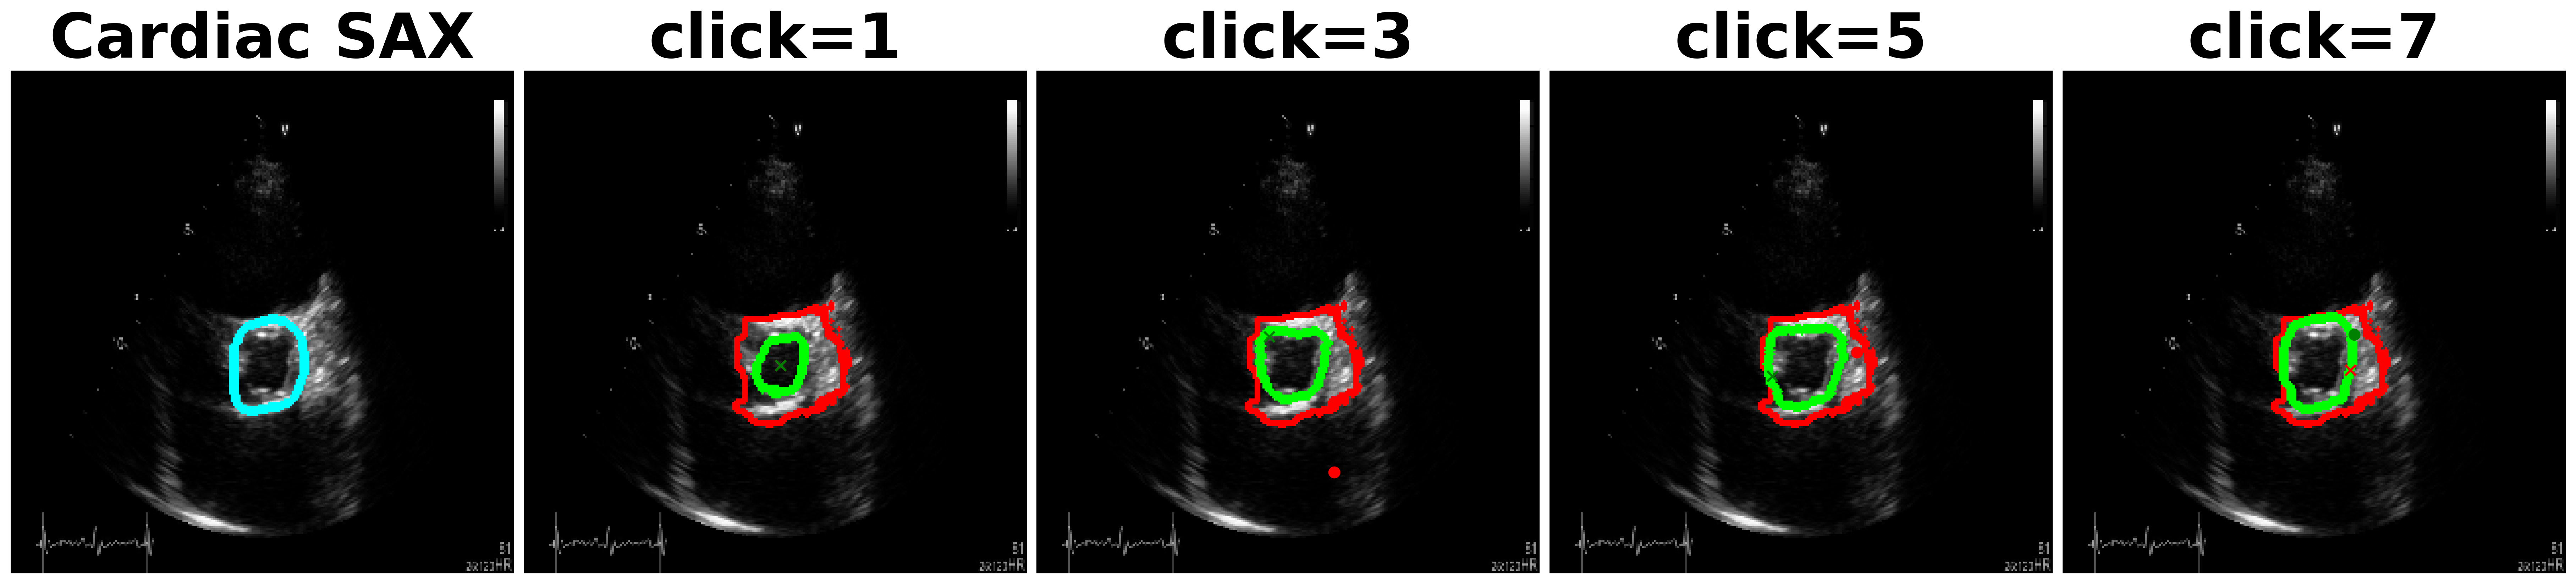

Utility of SAM[3] in medical imaging has been assessed recently in [27, 28, 29]. In an extensive experimental study [27], the authors find that while SAM obtains reasonable performance on different modalities, the performance is the poorest on ultrasound. This behavior is to be expected since ultrasound possesses unique characteristics like presence of scan cone, poor image quality and unique texture with speckles. Fig. 1a shows inefficiency of SAM and other methods on different anatomies, where after each click, our method outperforms consistently all the other methods.

SonoSAM achieves DSC on all data-sets and comfortably surpasses competing methods by a huge margin which struggle to cross even DSC. As shown in Table. 2, SAM model trained on natural images, under-performs significantly on ultrasound images often being poorer than SonoSAM in range of MaxDSC. Surprisingly, MedSAM which has been trained partly on ultrasound images is often the worst performer amongst all models, despite 3 of these datasets being ‘in-domain’ data-sets for MedSAM. Lack of training with clicks, severely hampers and infact deteriorates MedSAM’s performance. FocalClick model, performs reasonably on two data-sets - Liver and Fetal Head but takes several clicks to get to meaningful results, as shown Figure 7

One of the complaints with SAM model is that, the mask generated with user clicks (positive or negative clicks) are unintuitive and unpredictable. As shown in Figure 8, SAM often picks the entire FOV as the object and is unresponsive to multiple clicks. In contrast, SonoSAM’s responses are predictable, as demonstrated by smooth progression of predicted contours as shown in Figure 8